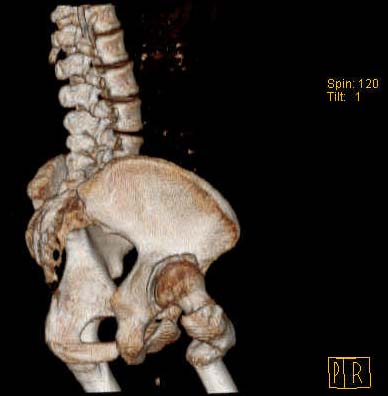

Уважаемые коллеги!Женщина, 35 летВ прошлом по поводу врожденного вывиха бедра перенесла операцию остеотомии по Шанцу

с удлинением правой ноги за счет бедра на уровне диафиза. В последнее время прогрессируют боли в правом тазобедренном суставе, порочное положение правой ноги, затруднена ходьба.Вопросы:1) Целесообразно ли эндопротезирование правого тазобедренного сустава?2) Целесообразный ли следующие действия: канал бедренной кости предполагаем вскрыть для введения ножки протеза на высоте угловой деформации, предполагаем низведение большого вертела с мышцами; протез будет подобран индивидуально, предполагается умеренная версия?В приложении рентгенограммы и трехмерная КТ.В цветном и более качественном варианте КТ размещена здесь

Наше общее мнение - проведение клиновидной остеотомии в зоне дополнительной точки опоры с ее иссечение и укорочением бедра, протезирование ножкой Вагнера.

Похожий случай представляем на ретгенограммах. Операция выполнена в 1996 г.